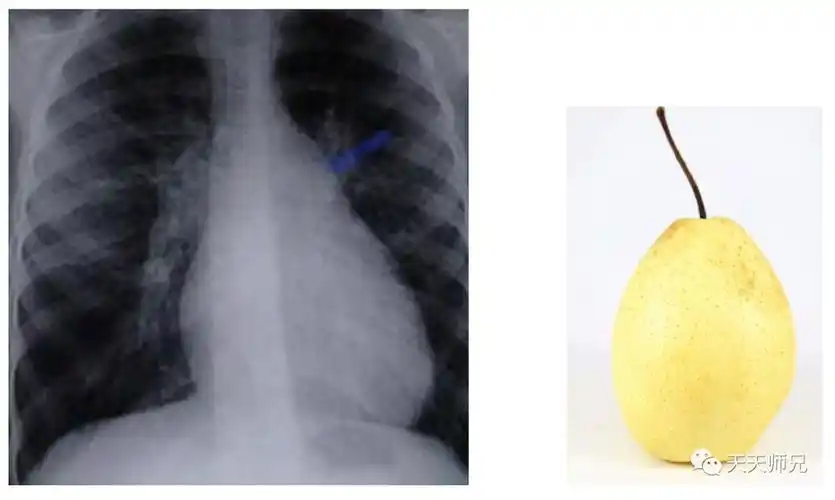

梨形心怎么回事 梨形心也叫做靴形心,是指心脏疾病而导致心脏形状

梨形心,靴形心,烧瓶心 :这也样看平片,想不会都难